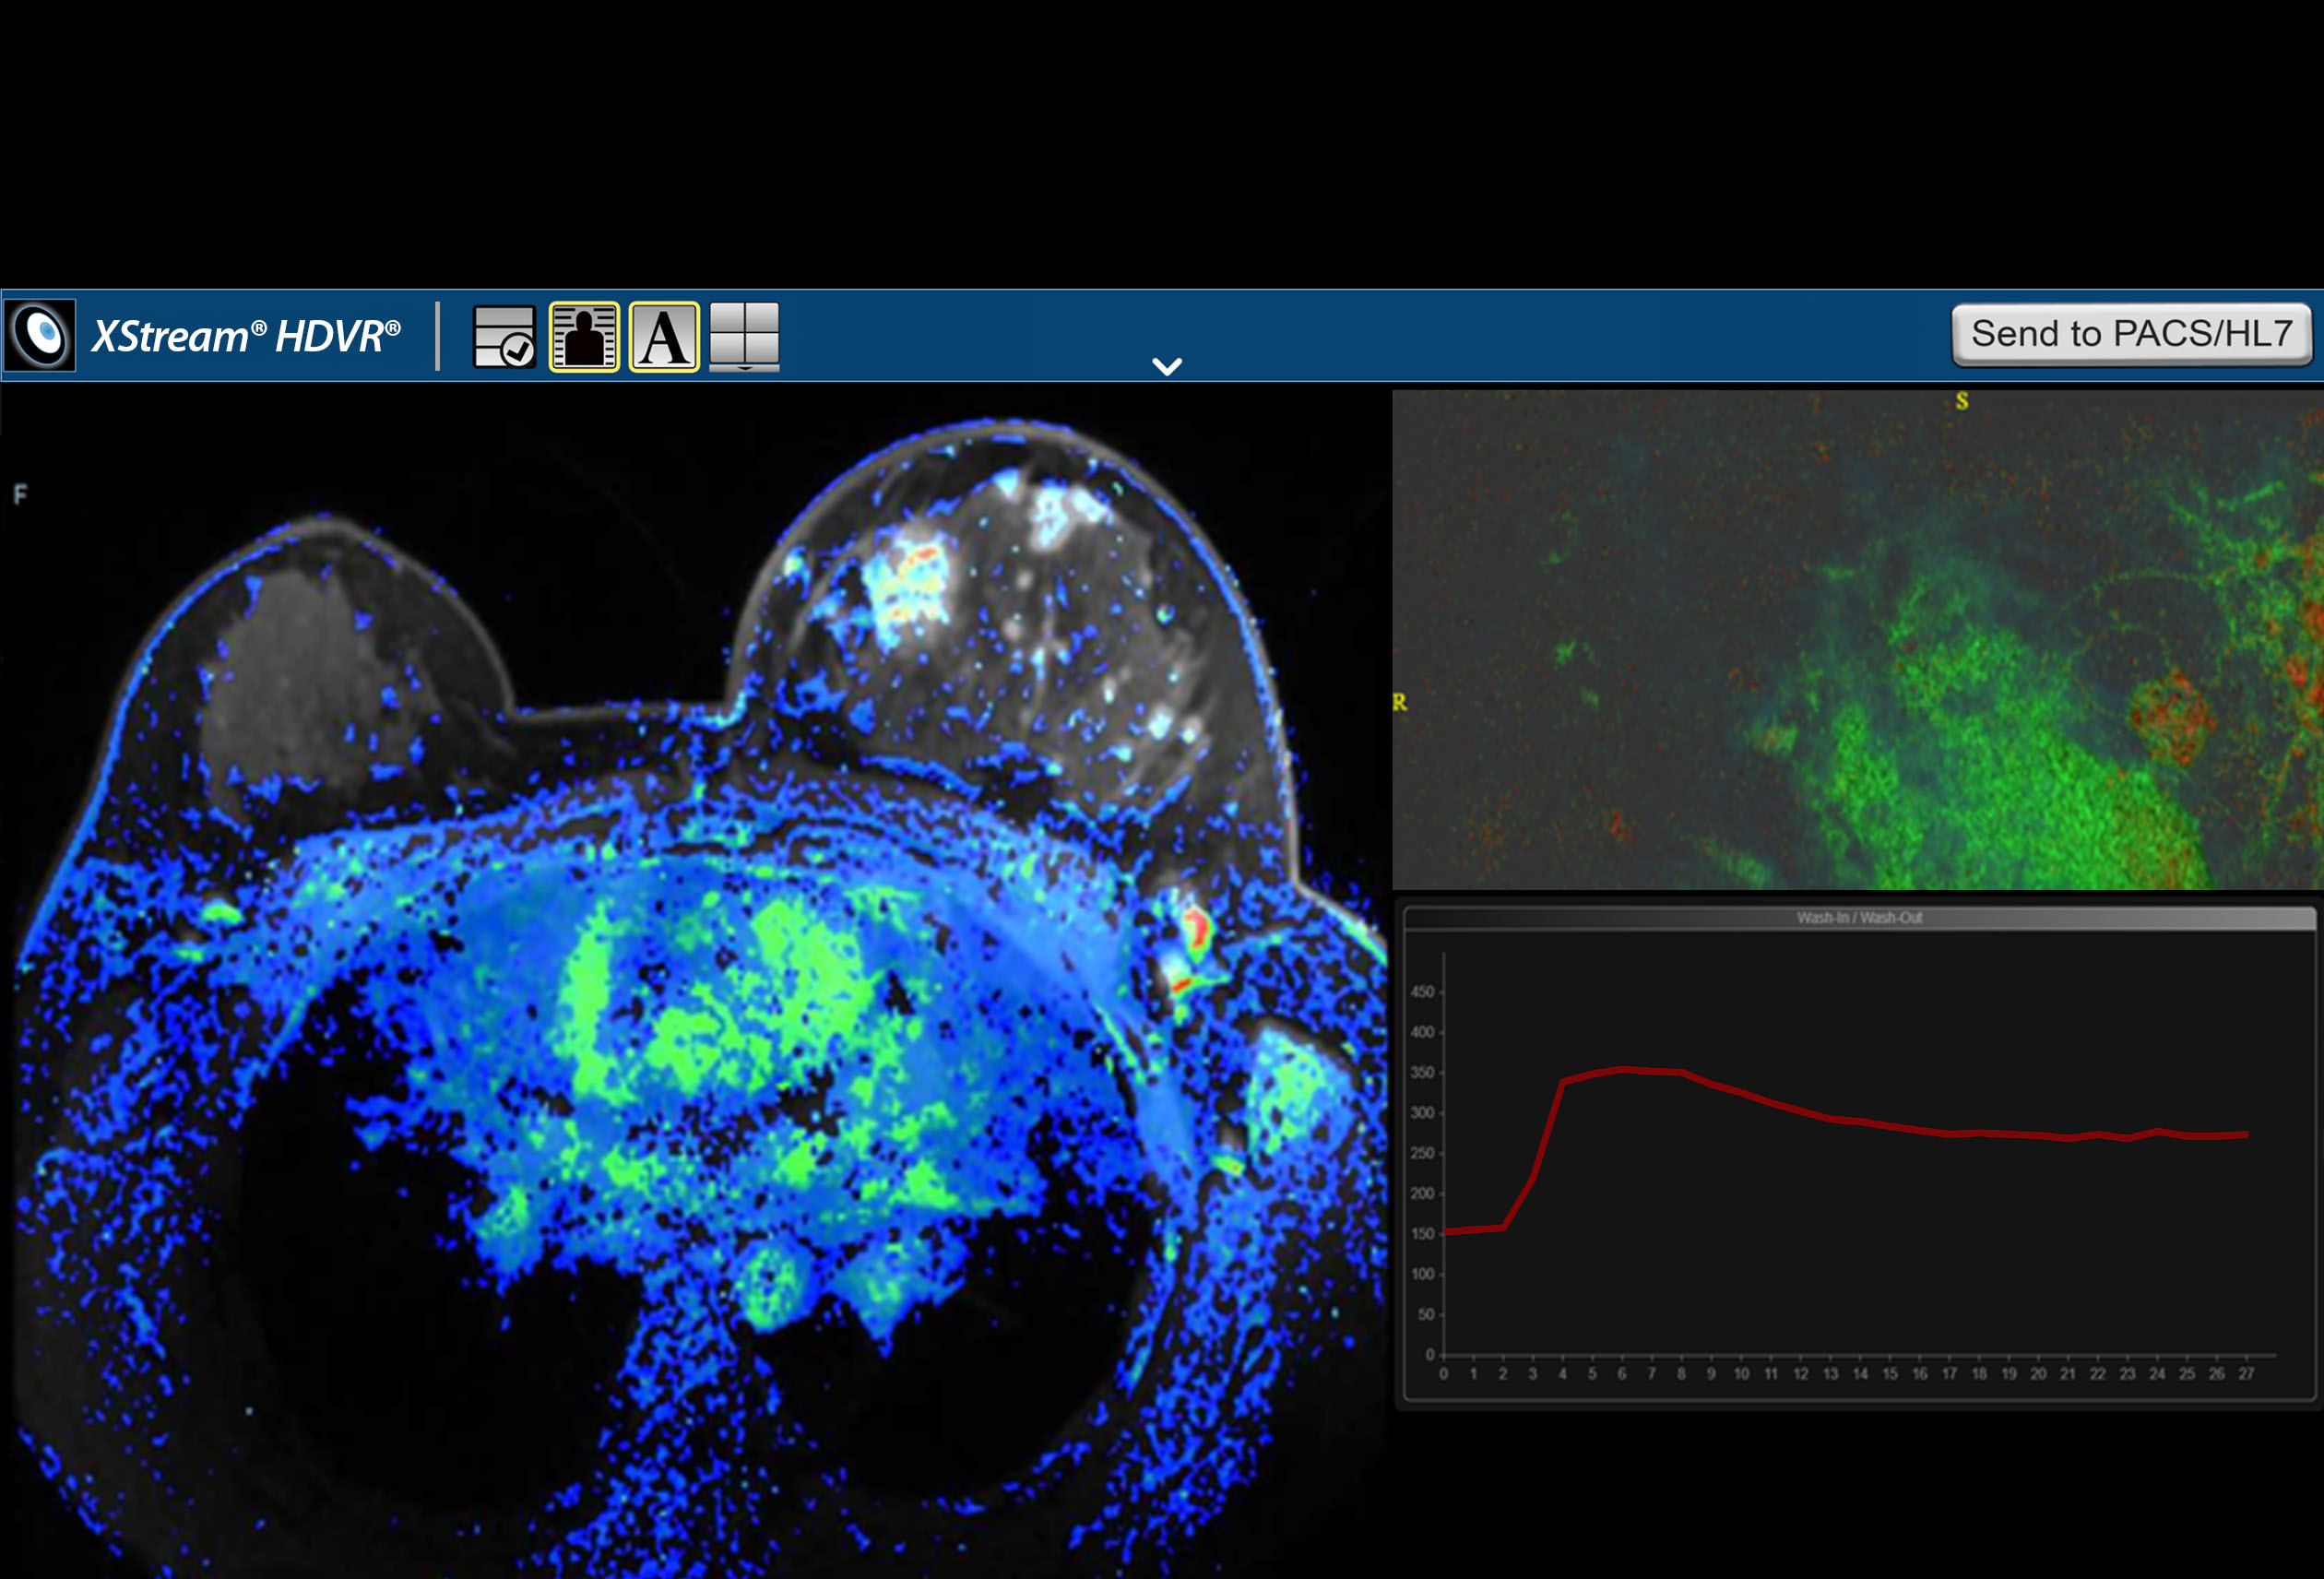

F.A.S.T. Multiparametric MRI Workflow

F.A.S.T. Multiparametric MRI Workflow